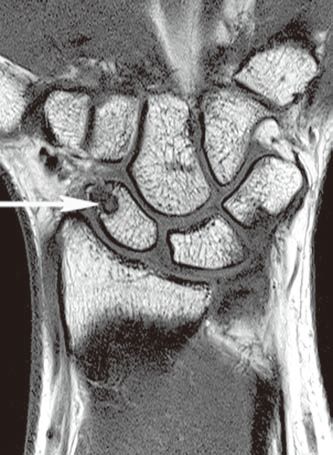

图1左腕手舟骨骨内腱鞘囊肿

左腕正位X线平片(A)示手舟骨远部骨内一小的透亮区。冠状位T1WI(B)示骨内病变呈低信号(箭)。冠状位(C)和横轴位(D)脂肪抑制T2WI示病变呈高信号,提示为液体(箭)